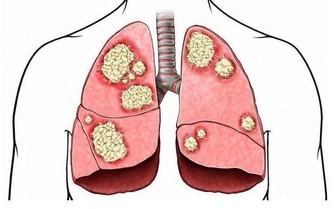

(2)骨質疏鬆

過遲絕經的婦女需要警惕,因為,55歲以後還未絕經,體內激素水平長期偏高,增加了子宮內膜癌和乳腺癌的風險。所以過了55歲未絕經的婦女,必須定期到醫院做B超檢查子宮內膜(有必要時還要做內膜活組織檢查),以及乳腺B超,防患於未然。